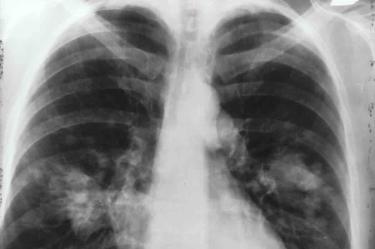

Muertes por cáncer de pulmón aumentarán por falta de diagnóstico temprano: INCAN

La mortalidad por cáncer de pulmón podría aumentar entre un 20 y un 35% debido a que durante esta pandemia, los pacientes no asisten a diagnosticarse, ni a sus consultas, por miedo a contagiarse

En México, la mortalidad por cáncer de pulmón podría aumentar entre un 20 y un 35 por ciento, debido a que durante esta pandemia de COVID-19, los pacientes no asisten a diagnosticarse, ni a sus consultas, por miedo a contagiarse o porque su hospital fue designado para atender a pacientes con coronavirus, alertó Oscar G. Arrieta Rodríguez Coordinador de la Unidad Funcional de Oncología Torácica del Instituto Nacional de Cancerología (INCAN).

“Si hay un retraso de tres o cuatro meses en etapas tempranas de este tipo de cáncer, se espera un incremento de la mortalidad de un 20 por ciento. Si está, localmente avanzado, el aumento será de alrededor de un 35 por ciento y en fase metastásica alrededor del 20 por ciento… a nivel global va a haber un incremento del 20 o 25 por ciento de mortalidad de pacientes con cáncer de pulmón por no asistir a recibir atención”, detalló.

Tras participar en el foro “Factores de riesgo y tratamiento para pacientes con cáncer durante la pandemia” de AstraZeneca, Oscar Arrieta Rodríguez, especialista del INCAN, añadió que los pacientes con cáncer de pulmón y diferentes tipos de leucemias, que se contagian de COVID-19 están registrando una mortalidad de alrededor del 55 por ciento.

Situación que representa el doble de riesgo, frente al 28 por ciento de mortalidad que se reporta en pacientes con otro tipo de neoplasias que se infectan del virus SARS-CoV-2.

Por lo anterior, considerando que el cáncer de pulmón ocupa el primer lugar de muerte dentro de todos los tipos de neoplasias, el oncólogo hizo un llamado a los pacientes para que no interrumpan sus tratamientos, porque cada día sin atención médica, reduce su tiempo de sobrevida.